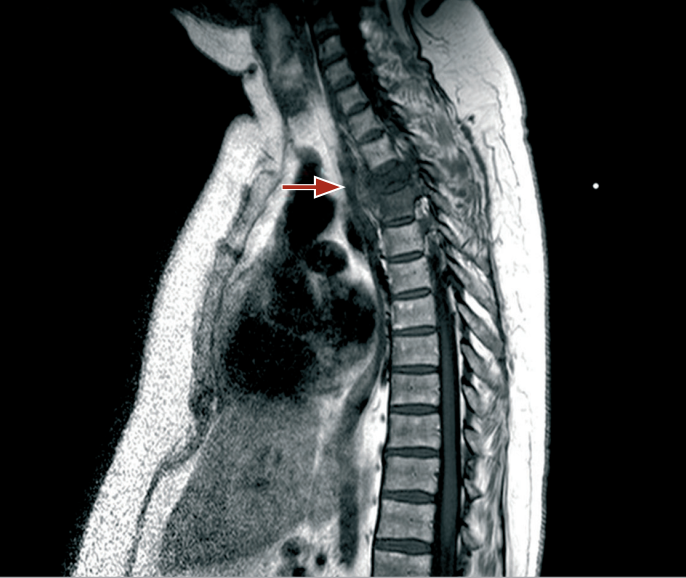

Spinal MRI with contrast revealed destruction of the D3-D4 intervertebral disc, osteolytic lesions of the vertebral bodies, and high signal intensity on STIR sequences, indicative of an inflammatory process with associated epidural and pleural abscess formation.

MRI of the spine with contrast agent: hypodensity of the vertebral body can be seen at T1